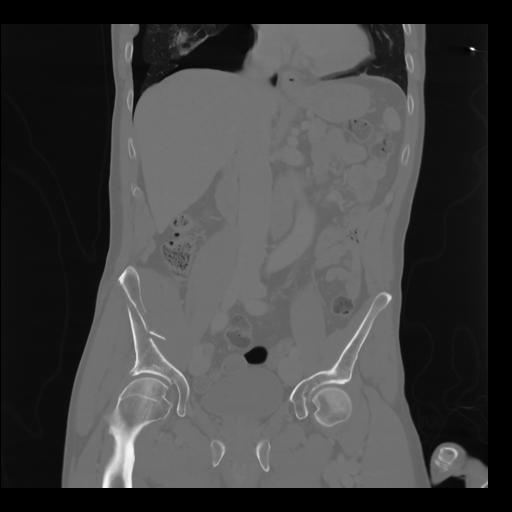

35 CUERPO,CE,Coronal,3.000,CUERPO,Coronal,